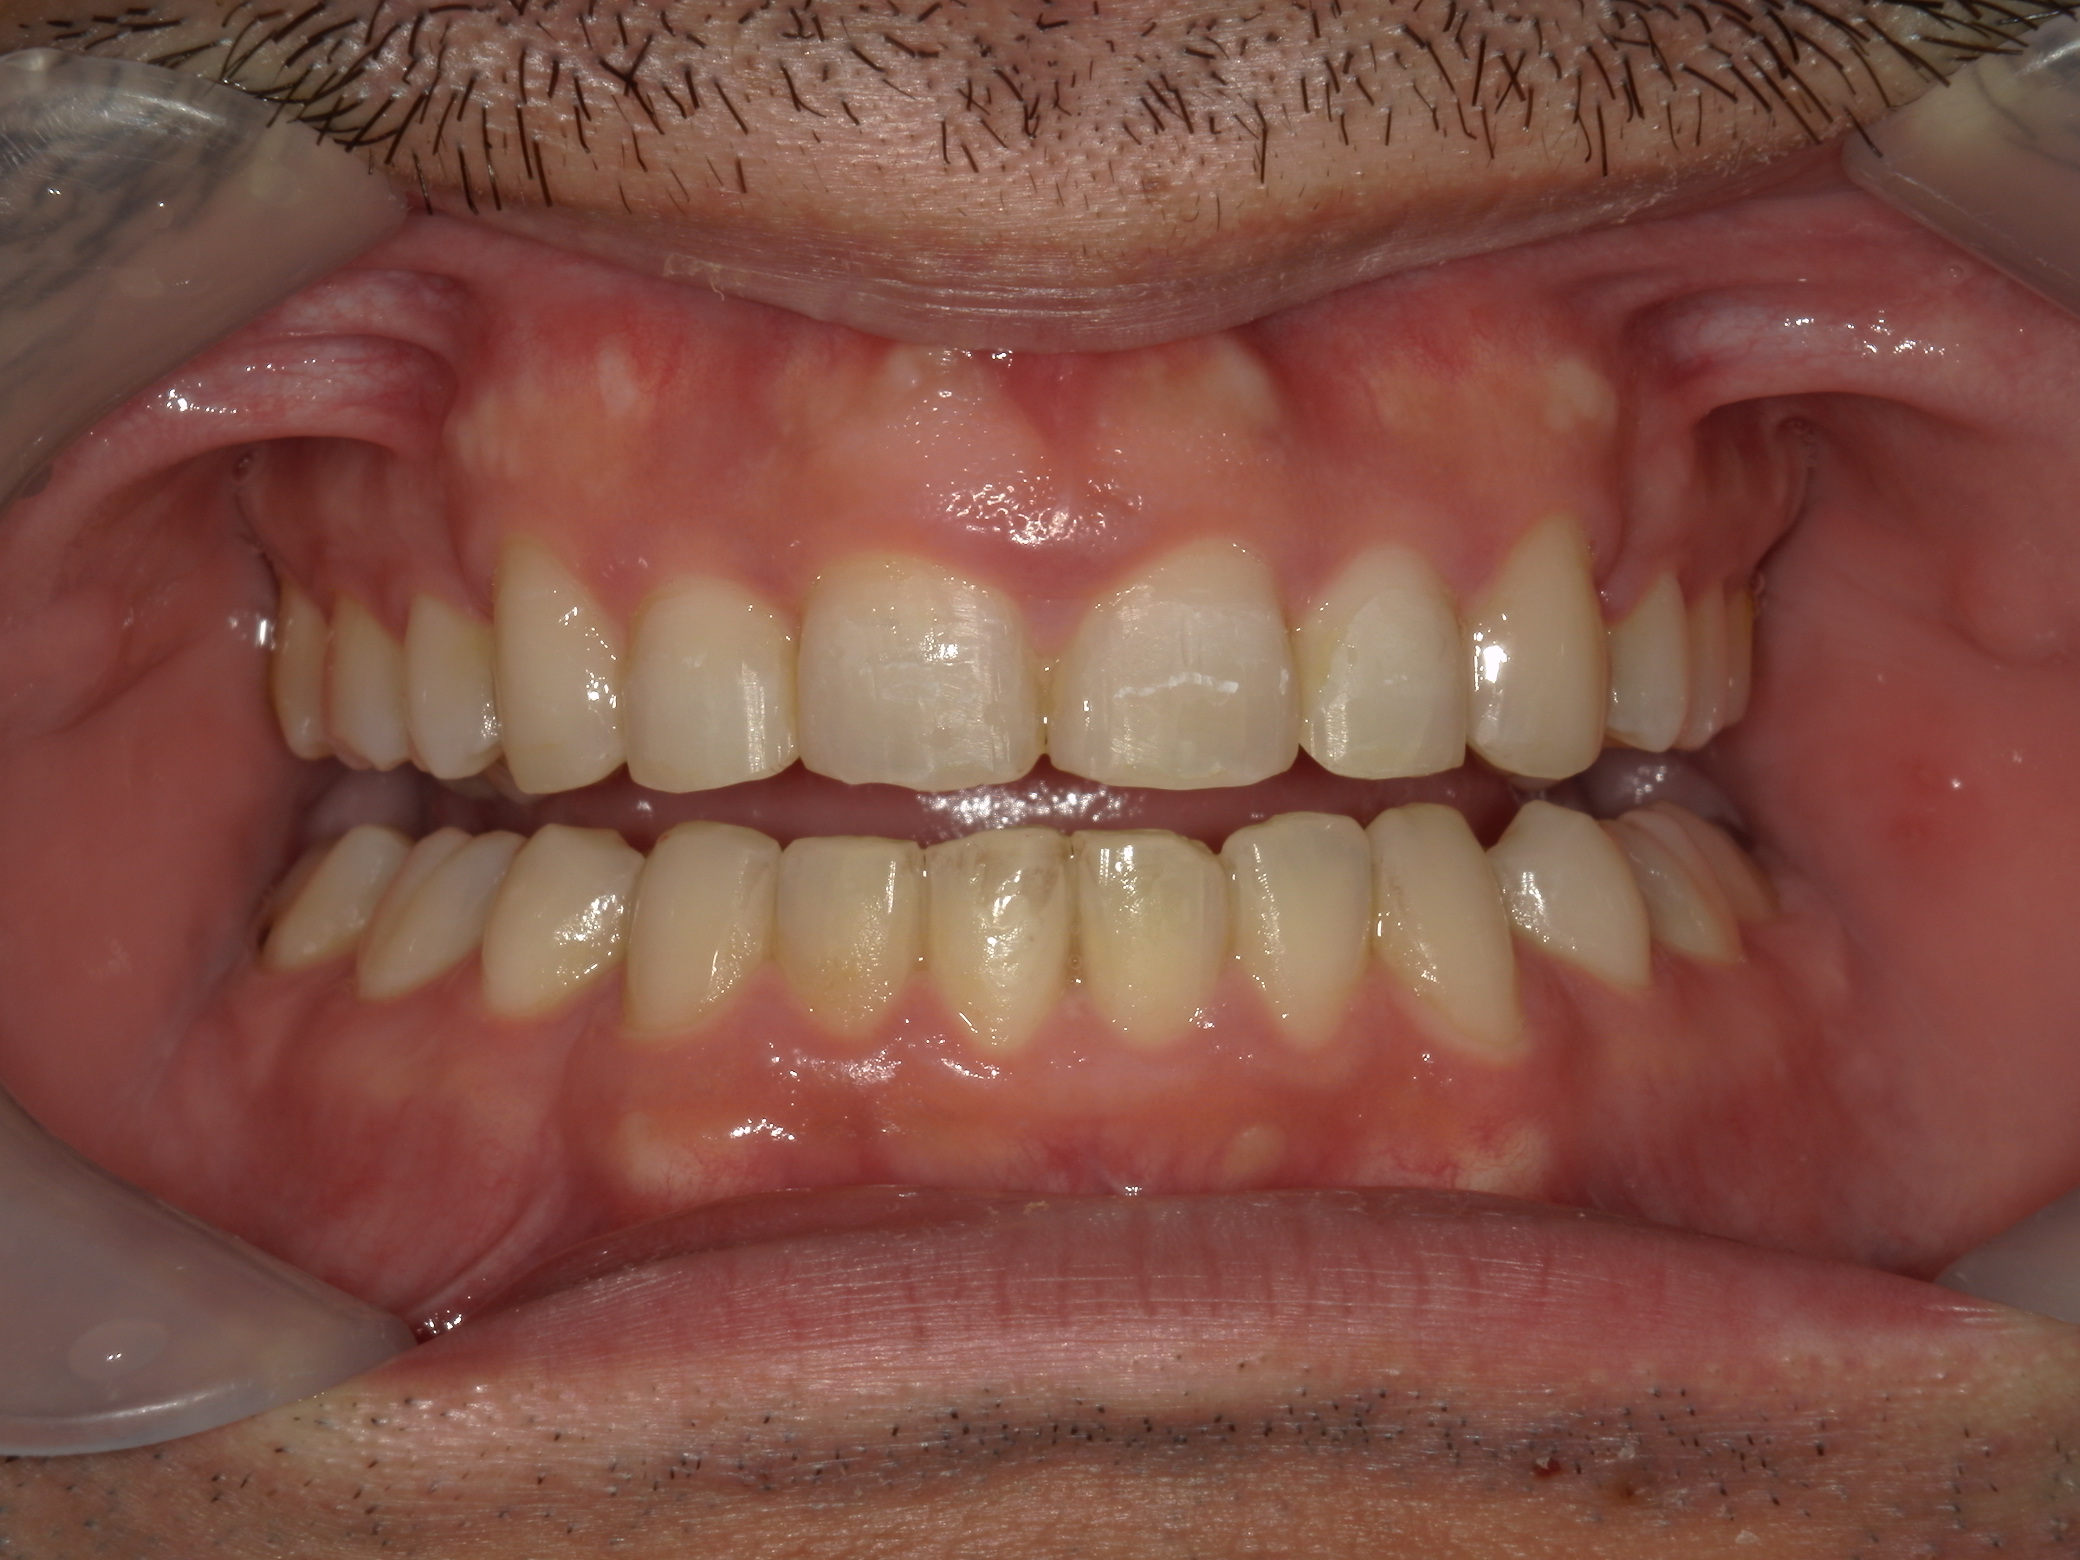

全顎ワイヤー矯正 症例(79)

主訴: 前歯が噛み合わない。歯並びが気になる。

上下左右 第一小臼歯(4本)、上下右 親不知(2本)抜歯。

ミニインプラント、アップライトスプリングを併用。

| 治療期間 | 3年7ヶ月 |

カテゴリー : ガタガタ(叢生) , 噛み合わせが深い(過蓋咬合)